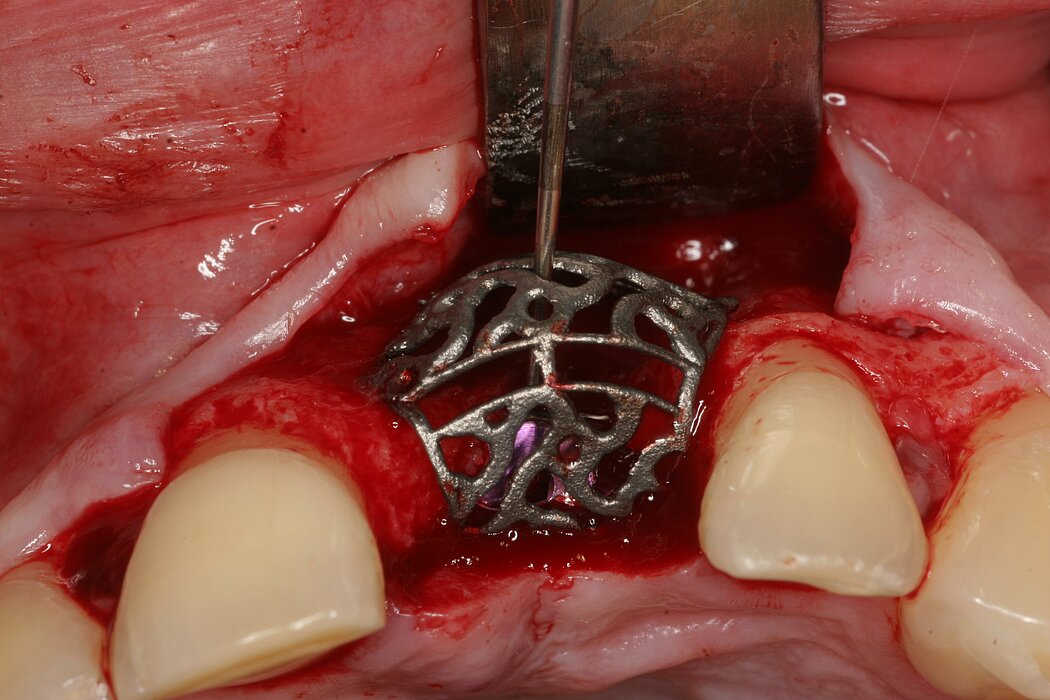

Yxoss CBR® - Individually made 3D Titanium Mesh (Case 1)

Larger and complex augmentations, especially with a combined horizontal-vertical defect morphology, still present a major surgical challenge. In these cases, the augmentation material requires a high level of regenerative ability, which can be achieved by mixing Geistlich Bio-Oss® and autologous bone. In addition, long-term stabilization of the augmentation material is necessary, which the ReOss® Customized Bone Regeneration (Yxoss CBR®) mesh structure can provide. The aim of this technique is to use the tried and tested material titanium in combination with modern CAD/CAM technology to achieve defect-specific, customized bone regeneration.

Advantages of Yxoss CBR® compared to conventional titanium mesh or titanium-reinforced membranes:

- Customizing can lead to a shortened operation time and fewer complications, as there are no sharp edges or restoring forces.

- Easier fixation - with one or two screws as needed - which is also possible in the coronal area.

- Incorporating a pre-determined break point also makes removal of the titanium mesh easier.

- The augmentation material can be determined individually in relation to autogenous bone and bone replacement.